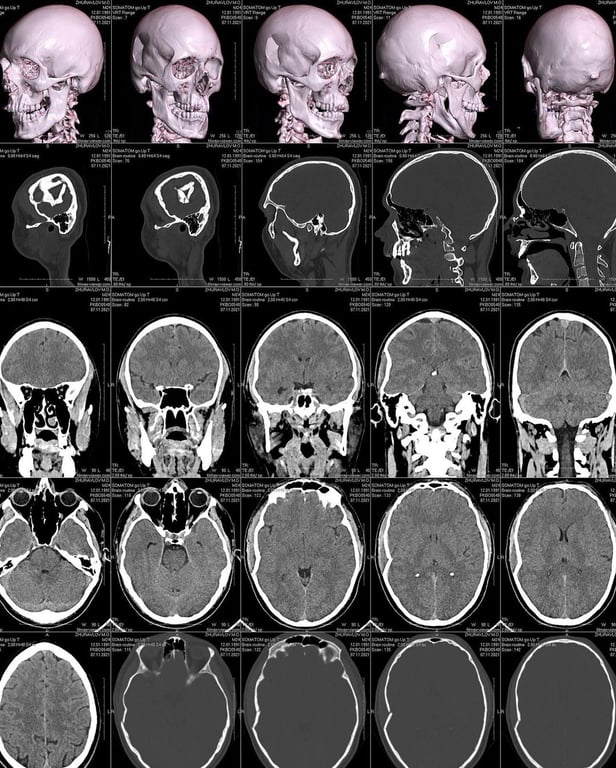

"Я был избит в собственном подъезде. Хирург сказал, что с такими травмами обычно в больницу приезжают уже в коме. Но мы с Дианой еще 12 часов после травмы ездили по всему Киеву делали обследования, компьютерную томографию и все остальное", - пишет Николай.

По словам Журавлева, он пережил операцию по удалению поврежденных костей черепа:

"Пару часов назад прошла операция по удалению поврежденных костей черепа. Через месяц нужна операция по внедрению в голову пластины. Никогда вас ни о чем не просил, но если есть возможность помочь, буду очень благодарен. Обещаю написать ещё больше классной музыки".